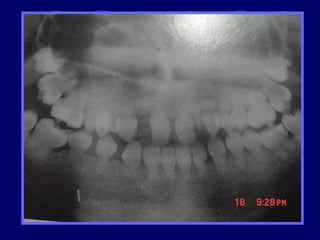

TAURODONTISMO

 cuerpo del diente se alarga, raíces cortas, furca

se desplaza hacia apical, cámara pulpar amplia

en sentido apico-oclusal

 Dx: radiográfico

 Etiología retraso en la vaina radicular de

hertwing en invaginarse horizontalmente,

hasta que esta cerca del ápice.

 Fx: 0.5 -5 %

 Se asocia a Síndromes congénitos, con

herencia ligada al sexo (Sx. Klinefelter)

 Se clasifica en tres según el grado de

afectación y la extensión de la cámara pulpar:

 Hipotaurodontismo: leve, la corona es 1/3 total del

diente, el cuello -1/3, y la raíz -2/3

 Mesotaurodontismo: la raíz se divide en el tercio

medio apical, la cámara pulpar es más ancha que

alta, 1/3 las tres porciones

 Hipertaurodontismo: la raíz se divide en el tercio

ápical o no se divide, la cámara pulpar es más alta

que ancha. La corona 1/3, cuello 2/3.

TAURODONTISMO  cuerpo deldiente se alarga, raíces cortas, furca se desplaza hacia apical, cámara pulpar amplia en sentido apico-oclusal  Dx: radiográfico  Etiología retraso en la vaina radicular de hertwing en invaginarse horizontalmente, hasta que esta cerca del ápice.  Fx: 0.5 -5 %  Se asocia a Síndromes congénitos, con herencia ligada al sexo (Sx. Klinefelter)

• 34.

 Se clasificaen tres según el grado de afectación y la extensión de la cámara pulpar:  Hipotaurodontismo: leve, la corona es 1/3 total del diente, el cuello -1/3, y la raíz -2/3  Mesotaurodontismo: la raíz se divide en el tercio medio apical, la cámara pulpar es más ancha que alta, 1/3 las tres porciones  Hipertaurodontismo: la raíz se divide en el tercio ápical o no se divide, la cámara pulpar es más alta que ancha. La corona 1/3, cuello 2/3.